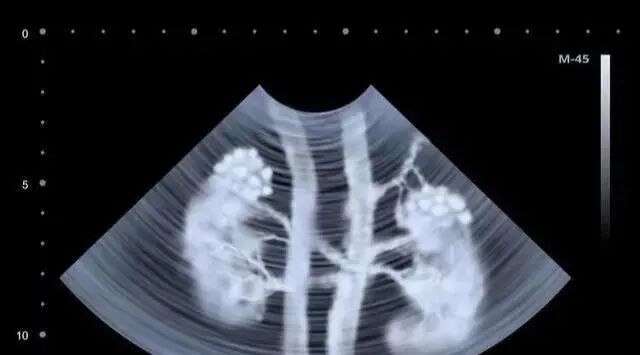

| 肾脏作为人体重要器官之一,就像是身体的“净水器”,每天需要过滤和清洁近 200 升血液,让代谢的废物排出体外的同时,调节体内的电解质和酸碱平衡, 以维持内环境稳定。假如肾脏开始罢工,肾功能便会出现异常,人体内代谢废物无法排出而大量堆积,会带来各器官的损伤,引起头昏、烦躁、食欲下降、心率紊乱等症状,引发肾脏疾病,最终可能导向尿毒症。当前我国慢性肾脏病患者数量超过1.2亿,总体现状为“三高一低”:高发病率、高死亡率和高医疗消费,以及公众的低认知。慢性肾脏病的死亡率还在增加,最大的问题不是没有防治的技术和手段,而是很多人不知晓、缺乏科学的数据,特别是慢性肾衰竭的透析率,只有美国的1/4。随着我国高血压、肥胖和II型糖尿病患病率的不断增加以及老龄化问题的加重,慢性肾脏病患病率很可能会继续升高。作为一种几乎完全不可逆的损害,慢性肾衰竭是指复杂发病原因及机制造成的慢性、进行性肾实质损害,导致肾脏明显萎缩,难以维持其基本功能,临床上以代谢产物潴留,水、电解质及酸碱失衡,全身系统受累为主要表现的临床综合征;因此其最主要的临床表现为代谢紊乱和各种不同系统的症状,表现相对多样。大部分肾病患者需要依赖和接受长期药物治疗来控制和延缓病情,终末期肾脏病消耗我国大量医疗资源。对于衰竭期和尿毒症期的患者而言,目前治疗方法主要是肾脏替代疗法,包括维持性透析治疗和肾脏移植。透析对医疗条件的要求较高的同时患者治疗过程相对痛苦,通过透析能替代部分肾脏功能,但是难以替代肾脏的内分泌、代谢功能等,导致临床死亡率较高。肾脏移植是尿毒症患者的有效治疗方式,但是供体数量相对有限,且有很高的配型要求和免疫排斥风险,术后并发症发生率较高;医疗费用高昂也是移植难以实施推广的一大原因。庆幸的是,随着干细胞技术的研究,肾衰竭的治疗也获得了很大的突破。它不仅在急性肾损伤模型治疗中显示出了有效作用,而且在治疗慢性肾疾病中也起到了一定作用。研究表明,体内注入了体外扩增的MSCs后,能对急性肾损伤产生保护作用并能加速肾功能的恢复。此外,MSCs亦能有效治疗慢性肾病。MSCs有一个特性,它们能够优先归巢到组织损伤区域或者炎症位点。研究显示,静脉回输的MSCs能够迁移到急性和慢性肾损伤模型动物的肾小球、肾间质、小管周围血管和肾小管。目前,MSCs归巢到损伤动物炎症位点的分子机制还不是完全清楚。不过,趋化因子在炎症部位募集的增多很有可能是引导MSCs迁移的重要原因,此外,MSCs的这种定向迁移和归巢方式与炎症部位趋化因子受体表达特征有关。近年来有研究证实,基质衍生因子、血小板衍生生长因子和CD44很有可能是调节MSCs归巢的候选对象,这是因为它们相应的受体会在肾损伤后表达上调。但归巢对于MSCs的治疗作用不是绝对必需的,表明MSCs分泌的多种因子的全身性募集才是充分诱导保护效应的主要原因。④ 通过干细胞再生来刺激其内源性修复。这些机制虽然在肾脏方面已经有了不同程度的研究,但其详细机制仍不清楚。干细胞进入人体后,干细胞会通过“迁徙”和“归巢”的诱导作用下到达受损的肾脏,这些回输的干细胞一方面能够根据周围微环境分化成新生的肾脏功能细胞;另一方面还能够“催醒”自身肾脏细胞“再生”,通过这种双靶向作用,使肾脏细胞得到最大程度的修复和再生,最后患者肝脏功能逐渐得到恢复。所以通过干细胞技术治疗可以阻止肾细胞的继续病变,阻断肾脏的纤维化进程,使血肌酐下降、预防肾性贫血、肾性高血压、肾性水肿等并发症的发生,也可使尿中蛋白、大便潜血等指标下降甚至转阴,使原发病得到调节和控制。即使肾衰竭的晚期,已经到了尿毒症的严重程度,也可实施干细胞治疗。一例62岁的印尼籍妇女,被诊断为胸部截瘫、慢性肾功能衰竭、糖尿病,长期肾脏受累,慢性肾功能衰竭2年,肌酐水平为11 mg/dL,无小便。采用脐带间充质干细胞方案治疗。鞘内注射1.6×107个间充质干细胞,静脉注射1.6×107个间充质干细胞。临床结果:鞘内注射和静脉注射完三周后,患者可移动脚趾,肾功能得到明显改善,肌酐水平降至9mg/dL。8个月后,患者可以拾起腿,肌酐水平为2mg/dL,小便恢复正常。干细胞输入体内后,通过干细胞的自动归巢作用,干细胞会自动转移到肾脏病灶,分化生成所需的各类细胞,从而达到修复肾脏固有细胞,恢复肾功能,重建肾脏血液循环,阻断和逆转肾脏纤维化进程。近年来基础研究干细胞治疗肾病过程中发现,干细胞可分化成肾固有细胞,肾实质细胞等,所以干细胞治疗后对肾脏功能具有良好的修复和重建作用。对于病变较重、病情常反复的患者,干细胞无疑是一种新的有效治疗手段,不仅能控制病情活动,还有可能治愈,对患者的病情带来极大的缓解改善。因为干细胞治疗可以修复受损肾细胞,避免肾功能的完全丧失。